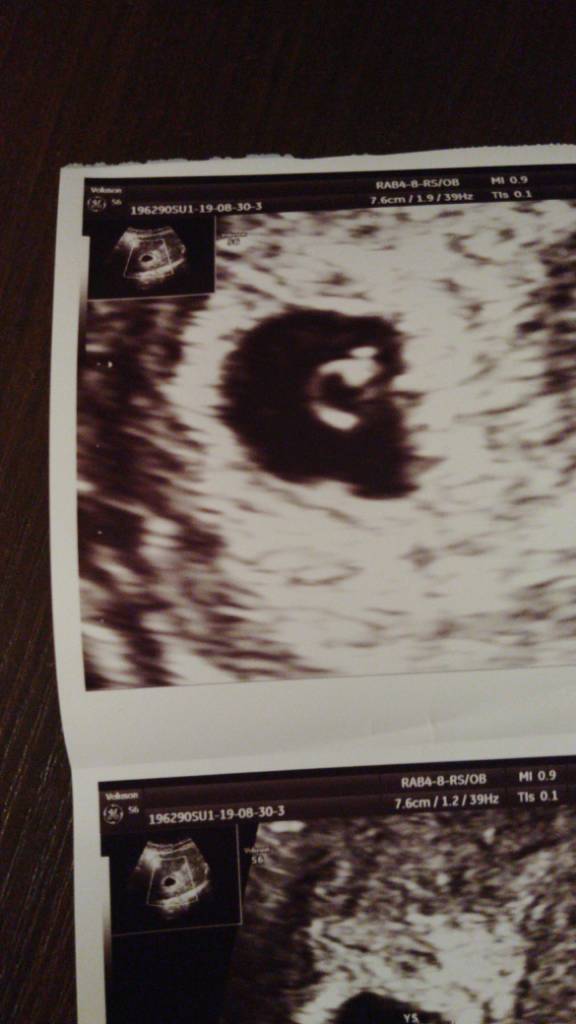

Bo jest taka metoda że jeśli zarodek jest po prawej stronie kosmówki to syn, a po lewej to córka [emoji16] Oczywiście to bardziej zabawa niż metoda na płeć, ale przy pierwszym synu się sprawdziło i teraz też wychodzi mi syn choć mam cichutką nadzieję na córkę [emoji16]

Najeczka a u mnie hahahaha??

IMG-20190830-WA0007.jpeg